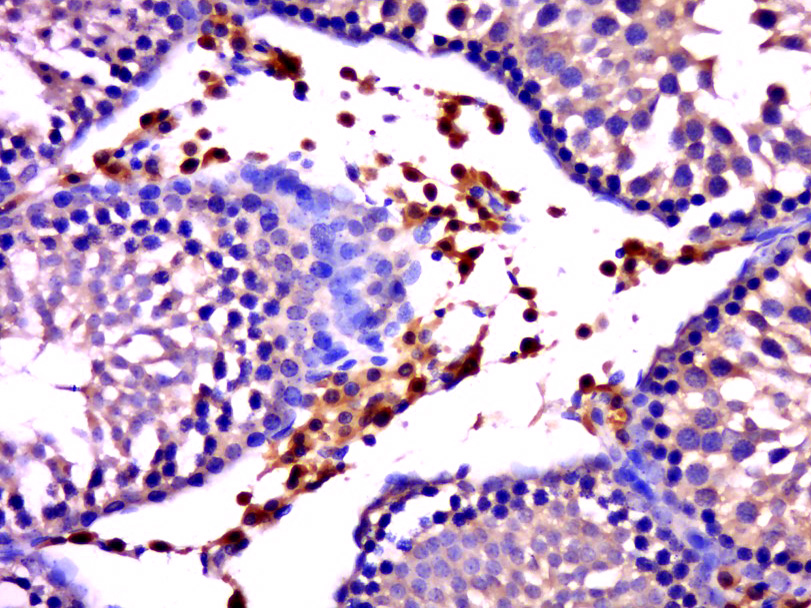

Paraformaldehyde-fixed, paraffin embedded (rat testis); Antigen retrieval by boiling in sodium citrate buffer (pH6.0) for 15min; Block endogenous peroxidase by 3% hydrogen peroxide for 20 minutes; Blocking buffer (normal goat serum) at 37°C for 30min; Antibody incubation with (GNAT3) Polyclonal Antibody, Unconjugated (bs-6149R) at 1:500 overnight at 4°C, followed by a conjugated secondary (sp-0023) for 20 minutes and DAB staining.

Tissue/cell: rat brain tissue; 4% Paraformaldehyde-fixed and paraffin-embedded; Antigen retrieval: citrate buffer ( 0.01M, pH 6.0 ), Boiling bathing for 15min; Block endogenous peroxidase by 3% Hydrogen peroxide for 30min; Blocking buffer (normal goat serum,C-0005) at 37℃ for 20 min; Incubation: Anti-GNAT3 Polyclonal Antibody, Unconjugated(bs-6149R) 1:200, overnight at 4°C, followed by conjugation to the secondary antibody(SP-0023) and DAB(C-0010) staining